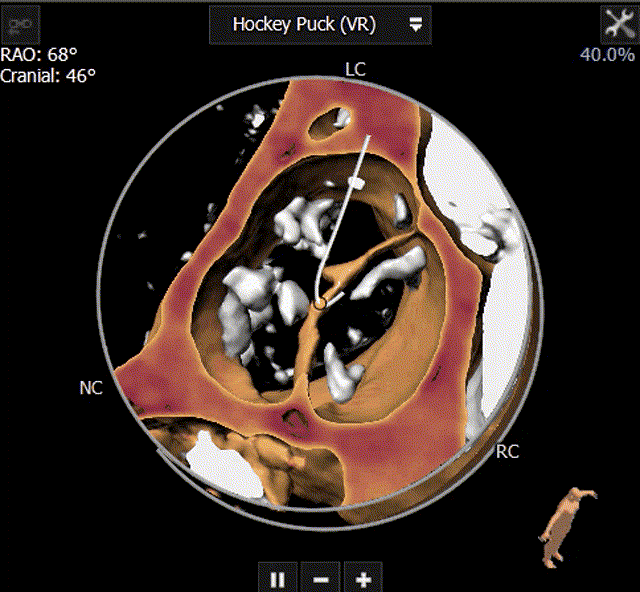

主动脉瓣CT评估:三叶瓣,双冠脉开口水平可,钙化分布较均匀。双侧髂股动脉内径可。瓣环长短径分别为17.9*25.1mm,周长为68.8mm,面积为358.1mm²。

主动脉根部整体形态(自流出道至升主动脉方向):